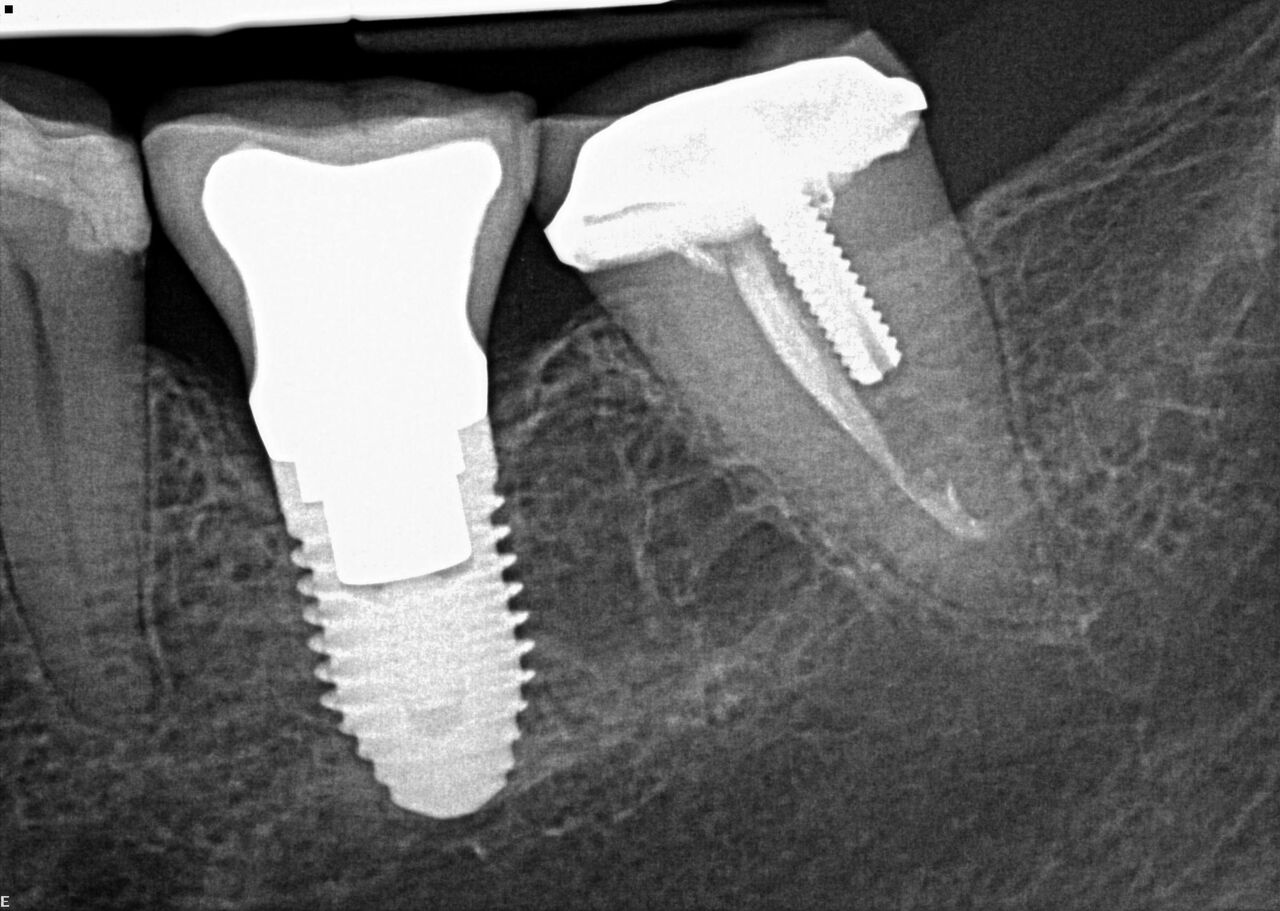

(20.) 6-month integration confirmation of Nos. 6 through 10.

Figure 20

(21.) 6-month integration confirmation of Nos. 6 through 10.

Figure 21

A 42-year-old man presented with a very loose bridge on Nos. 6 through 9 with periodontally compromised retainers on Nos. 6 and 9 (Figure 17 through Figure 19), and endodontically involved No. 10 with a calcified canal. Teeth Nos. 6, 9, and 10 were extracted, the sockets fully debrided, and pontic soft tissue on Nos. 7 and 8 sculpted to be symmetrical in soft tissue contour with the contralateral lateral incisor and central incisor locations. Implants were secured in position Nos. 6 through 10 (Figure 20) in excess of 45 Ncm, the bone was milled to provide unimpeded seating of temporary abutments, and temporary crowns were fabricated chairside and adjusted to be out of occlusion in centric relation and all excursions. The temporary crowns were cemented after extrusion of excess cement extraorally and the patient was prescribed antibiotics, analgesics, and instructed in postoperative care particular to immediately provisionally restored implants. At 6 months, integration was confirmed (Figure 20 through Figure 23) and after placement of scanning abutments, the implants and soft tissues were scanned. Final crowns were fabricated from the scanned images and were cemented after extrusion of excess cement extraorally (Figure 24 through Figure 26), and oral hygiene procedures were reviewed.

The patient was prescribed antibiotics and analgesics and instructed in postoperative care particular to immediately provisionally restored implants. At 6 months, integration was confirmed (Figure 14) and the patient returned to her dentist for restoration. The implants were restored with individual cement-retained crowns with a platform shift for No. 12 restoration from the 6-mm diameter of the implant to a 5-mm diameter of the final restoration (Figure 15 and Figure 16).